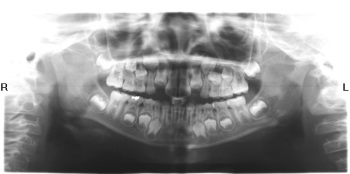

Hình trước và sau khi cấy implant

4. Cho phép chụp toàn bộ hàm răng và xương hàm, rất cần thiết trong chẩn đoán và điều trị nha khoa, đặc biệt trong cấy ghép implant, chỉnh hình răng, nhổ răng khôn, và những trường hợp phức tạp, cần có kế hoạch điều trị toàn diện.